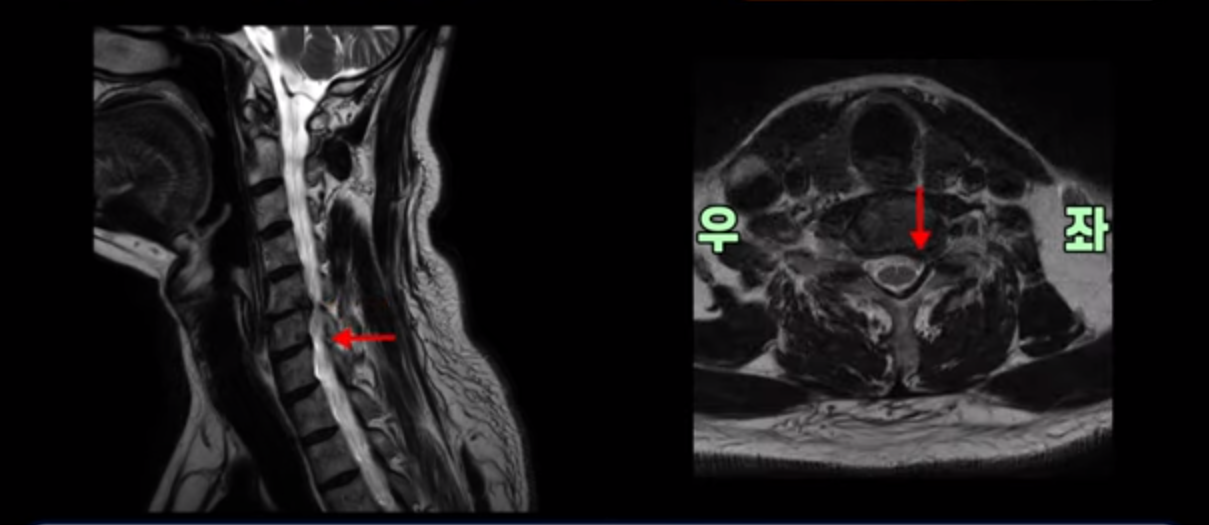

우선 이분 증상은 좌측 어깨와 팔 통증입니다. 이분 MRI를 보면 5번 6번과 6번 7번이 안 좋아 보입니다.

5번 6번에는 오른쪽과 왼쪽 모두 디스크 파열이 있고,

6번 7번에는 왼쪽으로 디스크가 밀려 나와 있습니다.

왼쪽으로 신경이 빠져나가는 추간공을 보면 보시다시피 5번 6번과 6번 7번 신경 구멍이 아래나 위에 비해 막혀있는 게 보입니다.

디스크도 밀려 나와 있고 협착도 있는 겁니다.

이분 왼쪽 어깨와 팔 통증이 갑자기 생긴 이유는 5번 6번 디스크 또는 6번 7번 디스크가 갑자기 밀려 나온 것이 원인일 것으로 보이는데, 그럼 이 디스크들이 밀려 나와서 신경을 자극하거나 누르는데 어떻게 이게 수술 없이도 좋아질 수 있는 걸까요?